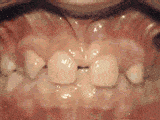

第七种: 牙列稀疏,牙槽骨过长,或者牙齿少,导致排列太宽松,零零散散,经过矫正后的是这样的。

第八种: 牙列稀疏,牙槽骨过长,或者牙齿少,光头强就是这类。导致排列太宽松,零零散散,经过矫正后的是这样的。